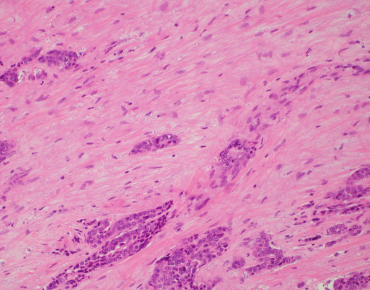

TRAIN YOURSELF

Incorporation of TILs in the Residual Cancer Burden Index

Artifical Intelligence / Deep Learning / Machine Learning approaches to TIL-assessment